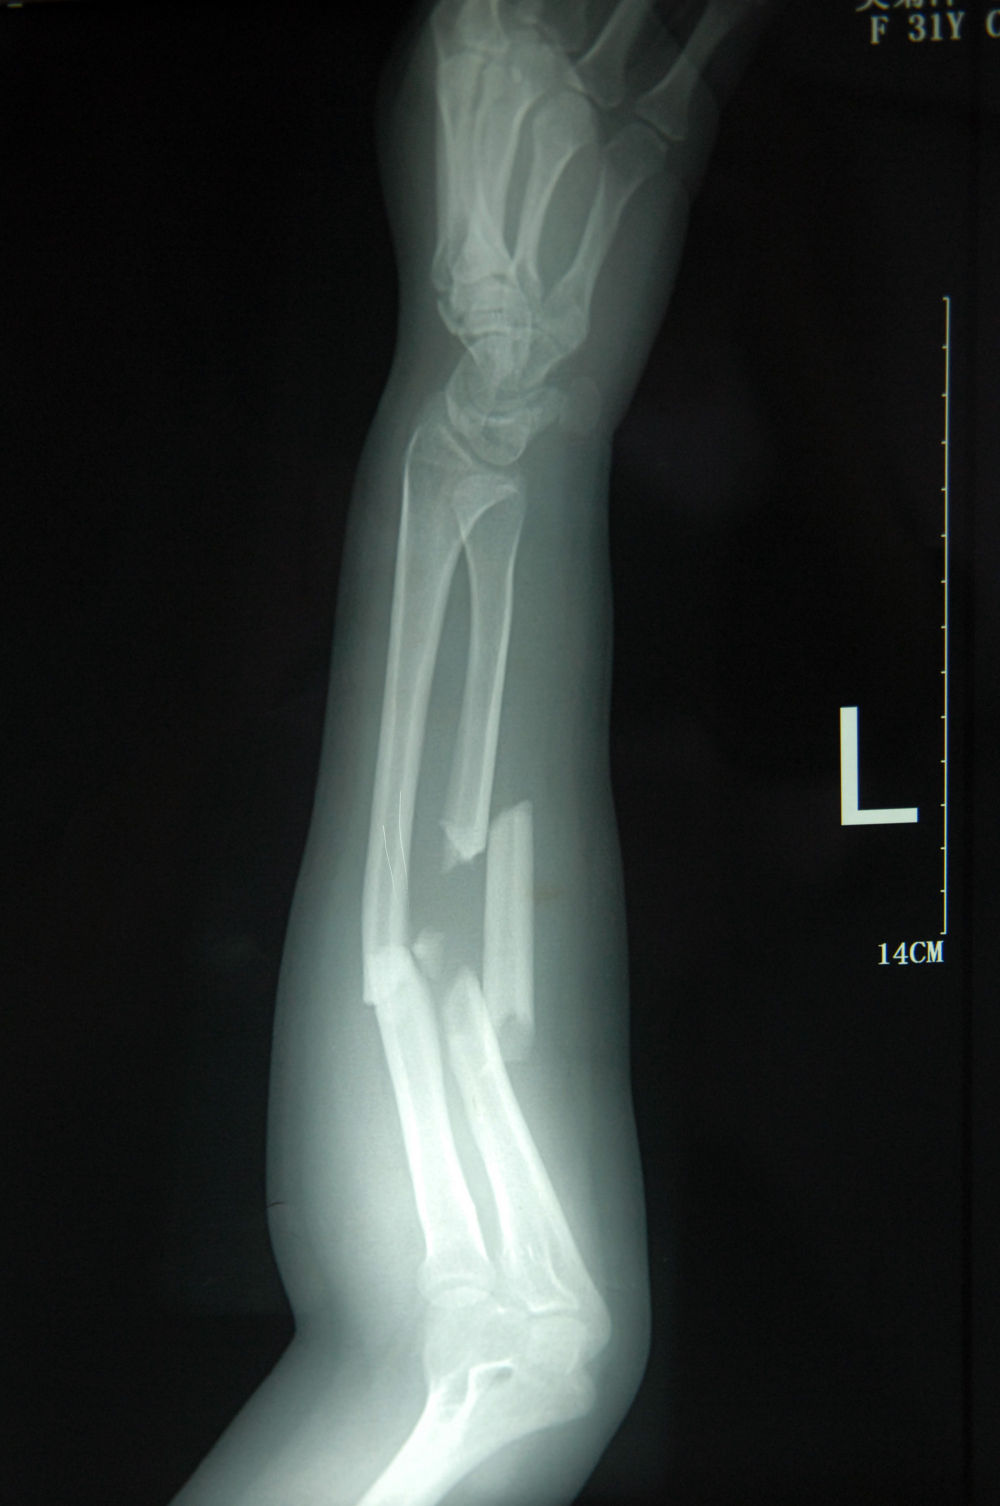

左腿ap外侧骨折x线片.

左小腿骨折x线片

21岁 女 胫骨螺旋性骨折 需要手术么 有x片